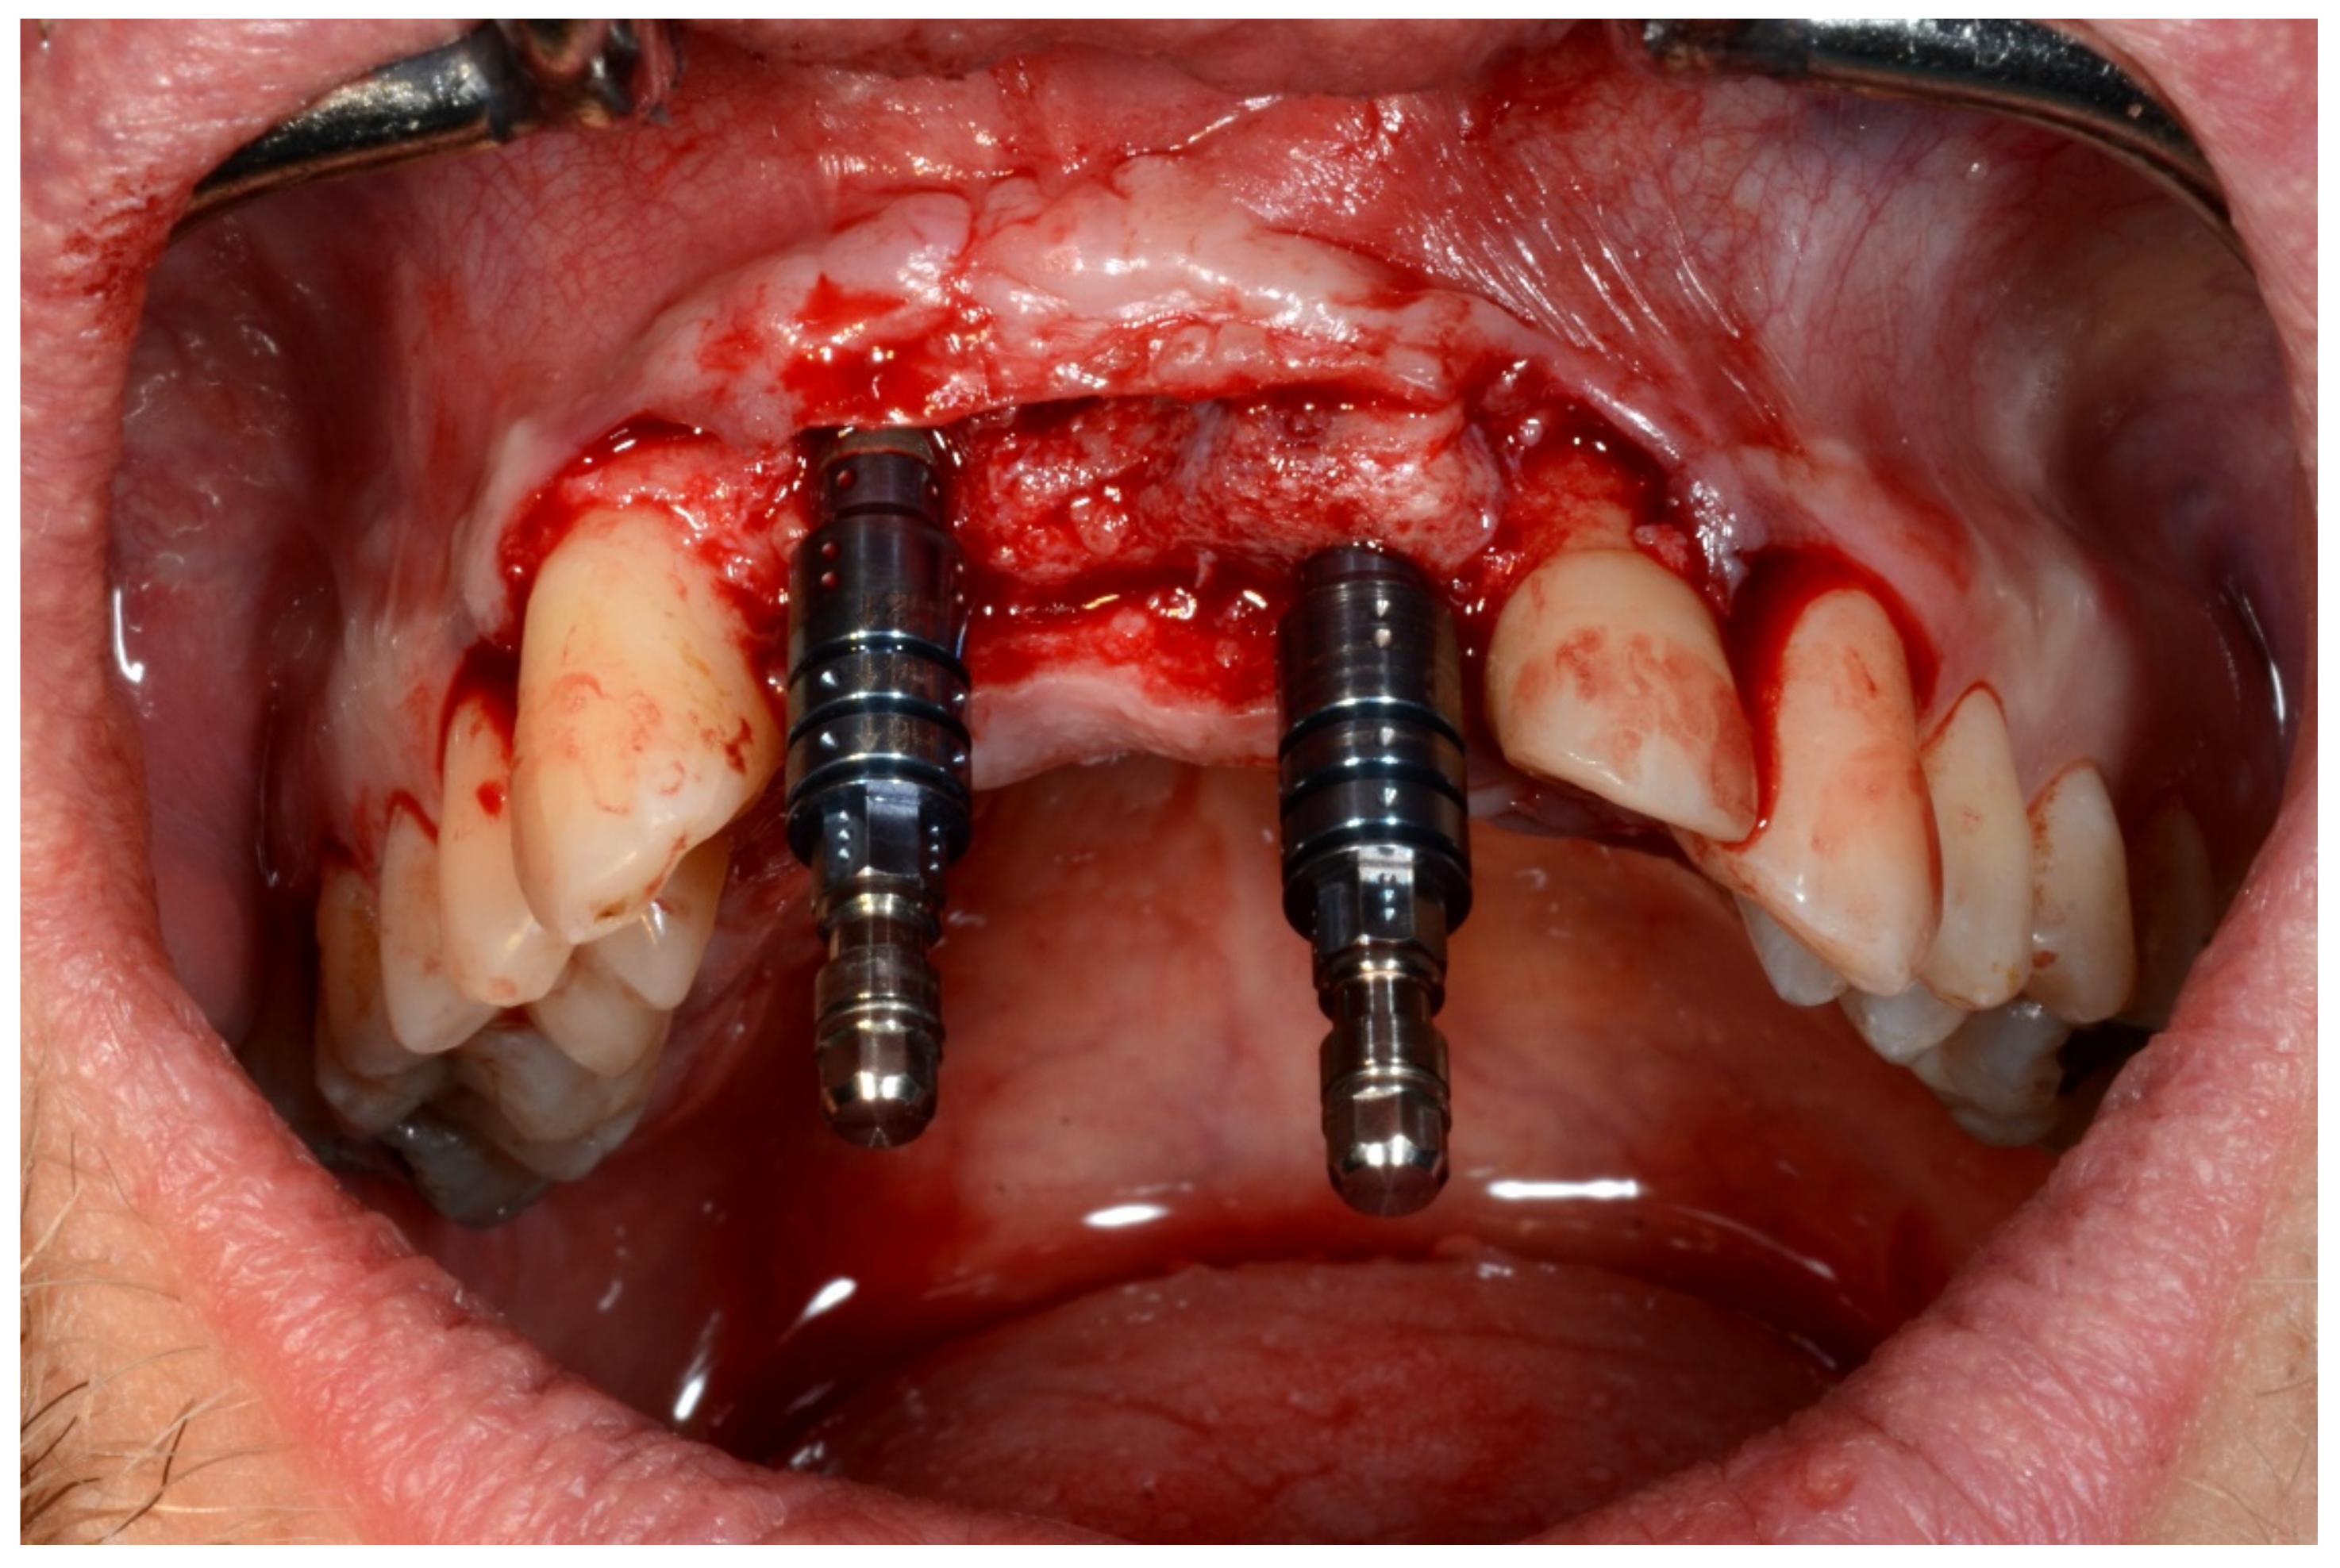

6.1.4. Intra-Operative Documentation:

In November 2017, two guided dental implants were placed at sites # 12 and # 21 (Figure 7, Figure 8, Figure 9, Figure 10 and Figure 11).

Figure 7.

Surgical drilling guides temporarily supported by teeth on the right and left sides.

Figure 8.

Implant bed preparation by using guided drills inserted into specific ad hoc drill handles.

Figure 9.

Guided implant insertion.

Figure 10.

Frontal verification of the parallel placement of the implants.

Figure 11.

Lateral verification of the parallel placement of the implants.